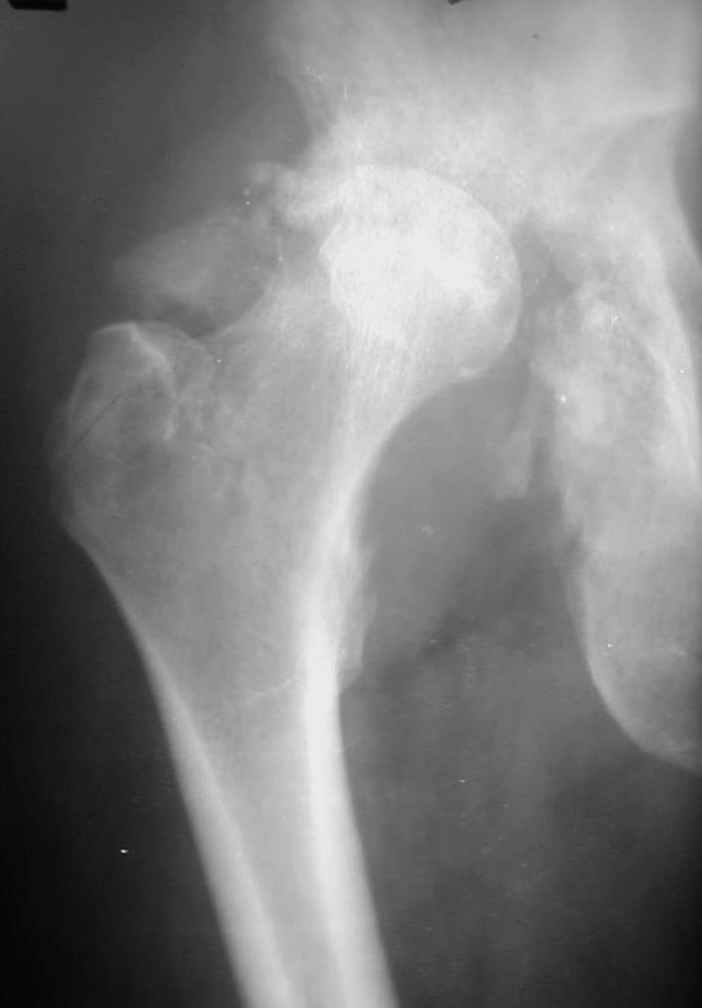

Уважаемые коллеги! На консультацию пришел молодой человек 23 лет с застарелым задним вывихомбедра. После травмы прошло 2,5 ГОДА.

Были переломы бедра и голени на этой же стороне, которые благополучно срослись после остеосинтеза. вывих бедра был пропущен. В настоящее время ходит без дополнительной опоры, есстественно, сильно хромает, выражен болевой синдром, парез седалищного нерва. Сформировался неоартроз в подвздошной области, виден неправильно сросшийся перелом задней колонны, сгибание в суставе до 80.